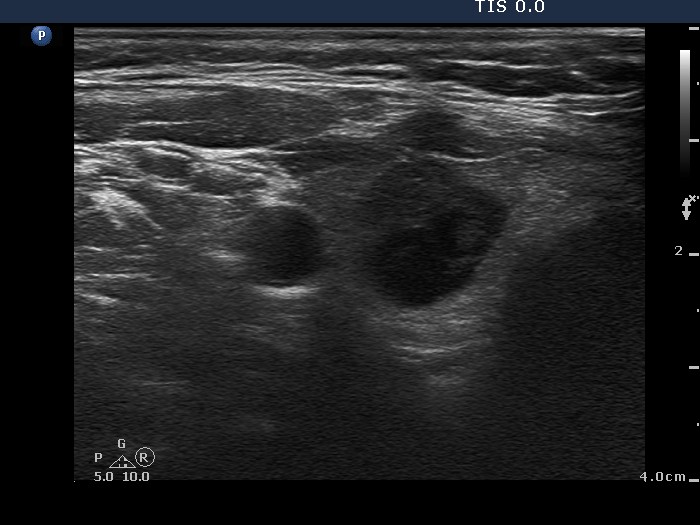

Benign hyperplastic nodule (histological diagnosis) - case 80 |

Papillary carcinoma (histological diagnosis) - case p057 |

The two cases differ in the lack and presence of punctate echogenic foci, benign (left) and malignant (right) case, respectively.